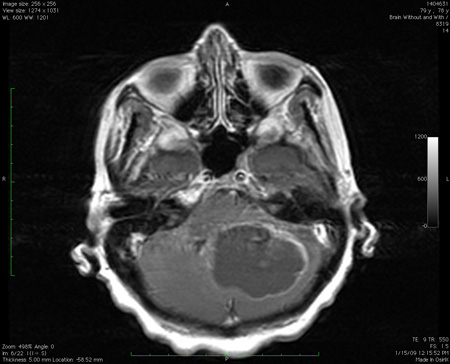

Work-up with imaging of the brain (CT scan, MRI with diffusion-weighted imaging sequence) is required to look for signal changes associated with stroke, demyelination, or cerebellitis.[128][132][133][134] CT imaging in children necessitates the use of dedicated paediatric protocols to minimise radiation exposure.[134][Figure caption and citation for the preceding image starts]: Acute bilateral cerebellar infarct, as seen on diffusion-weighted imaging sequence magnetic resonance imageFrom the collection of Dr S. H. Subramony; used with permission [Citation ends].

[Figure caption and citation for the preceding image starts]: Cerebellar infarct as seen on fluid-attenuated inversion recovery sequence magnetic resonance image: note secondary oedema and effacement of the fourth ventricleFrom the collection of Dr S. H. Subramony; used with permission [Citation ends].

In any patient presenting with chronic/subacute ataxia, MRI of the brain with and without contrast should be done.[133] Most of the entities in this subgroup can be definitively diagnosed based on clinical history, the nature of clinical signs, and the imaging abnormalities. The only situations where such patients may have similar problems in the family are some rare familial tumour or malformation syndromes such as von Hippel-Lindau syndrome.[Figure caption and citation for the preceding image starts]: Large mass lesion in the cerebellum with pressure effects, as seen on MRIFrom the collection of Dr S. H. Subramony; used with permission [Citation ends].